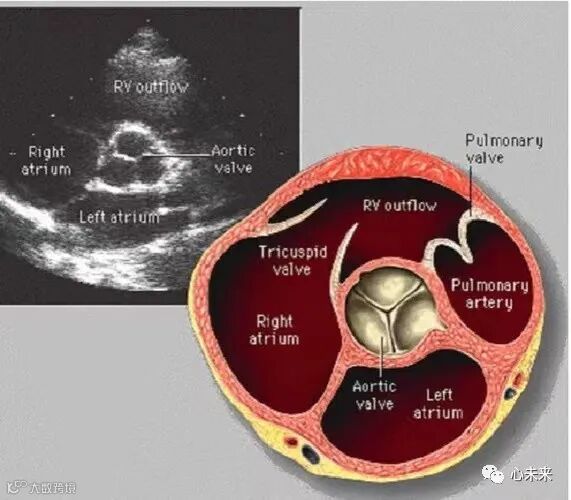

冰晶智能成立于2021年,面向结构性心脏病、电生理市场,推出下一代高清晰度、高操控性的HD-ICE产品,以填补国产空白,提高心脏介入手术的有效性、安全性。

公司专注于心血管介入影像,立足声学基础,以影像为手段,以数字化医疗革命为方向,为心脏与血管疾病设计、开发、生产专用的数字化介入影像产品,致力于推动数字化心血管介入影像学的发展,用数字化赋能心脏血管疾病诊疗全场景全流程。

HD-ICE采用了业内首创的新一代声能转换系统,可有效提升信号采集、传输效率及图像清晰度;

HD-ICE系统采用了国产首创的高清心脏图像专用处理系统,运用业内最新的软波束算法技术,有更快的成像速度,从而可以满足更多的临床需求